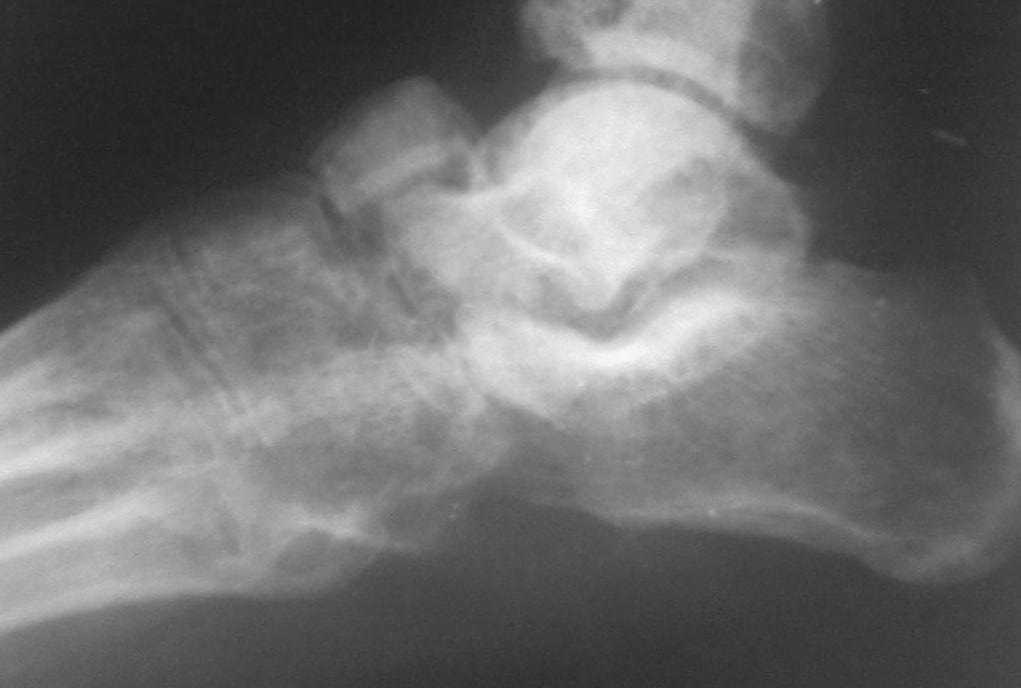

Застарелый вывых ладьевидной кости стопы |

Обратился больной 46 лет. 3 месяца назад получил травму левой стопы в результате ДТП, живет в отдаленный степной зоне, лечился у местного табиба.

Ходит при помощи двух костылей, наступая на пятку, на передный отд стопы наступать не может из-за боли, умеренная отечность стопы и деформация в обл. ладьевидной кости, движения в голеностопном суставе в польном обьеме, в средном отд ограничены и болезненны.